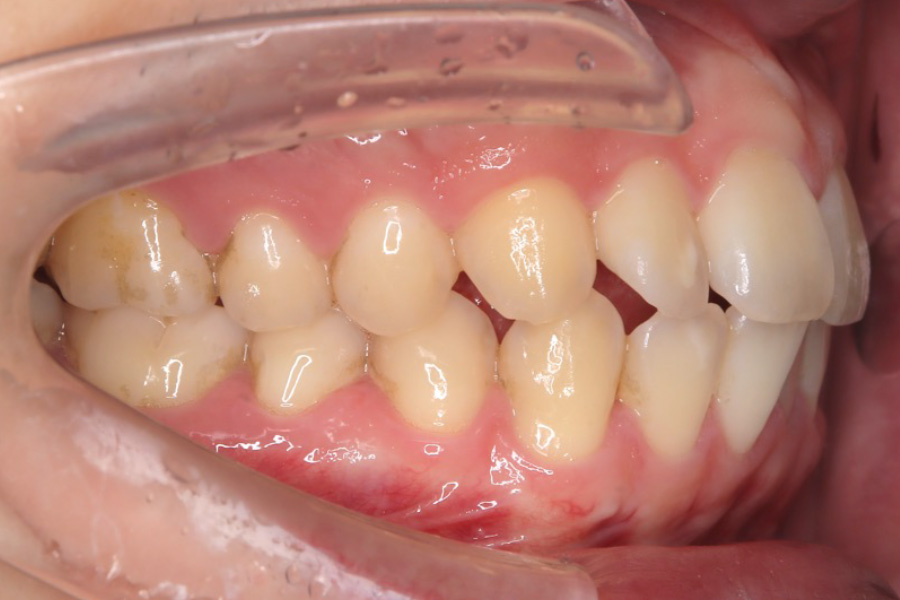

治療前

主訴 歯のガタつき

治療内容 インビザライン矯正

非抜歯